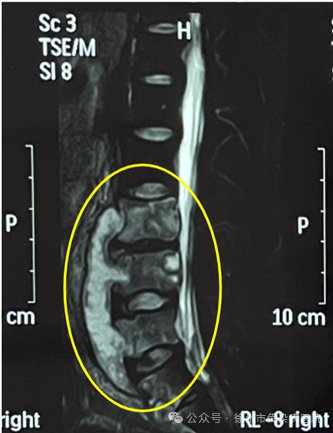

患者就医时有无肺结核病史,影像学检查X线、CT、MRI可以观察到骨骼的异常改变,如骨质破坏、骨髓炎、骨膜反应等。血液检查γ干扰素释放试验、结核菌素(PPD)有助于诊断。明确的诊断需要在病灶部位组织活检或脓肿抽吸,通过病理学检查、病原学检查确诊。